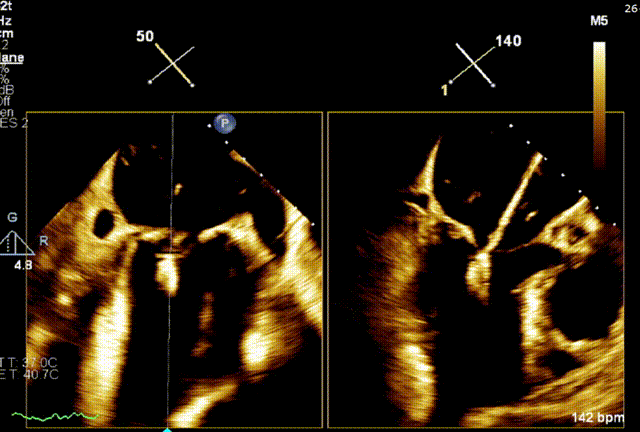

术前1区X-Plane反流情况

经食道超声提示,患者二尖瓣P1 commissural脱垂、腱索断裂合并重度反流(Carpentier II型/DMR4+)。

二尖瓣后瓣环明显钙化;主动脉瓣轻度钙化;三尖瓣中度功能性反流(FTR2+)。左房明显扩大;左室壁非对称性肥厚,以室间隔基底段肥厚为著(HOCM)。左室整体收缩功能正常。

二尖瓣环AP径33mm,二尖瓣后瓣环明显钙化,房间隔拟穿刺高度40mm;二尖辦脱垂宽度5.7mm,脱垂高度7.7mm,二尖瓣1区前叶长度29mm,后叶长度19mm,二尖瓣2区前叶长度23mm,后叶长度14mm,MVA=4.0cm²。